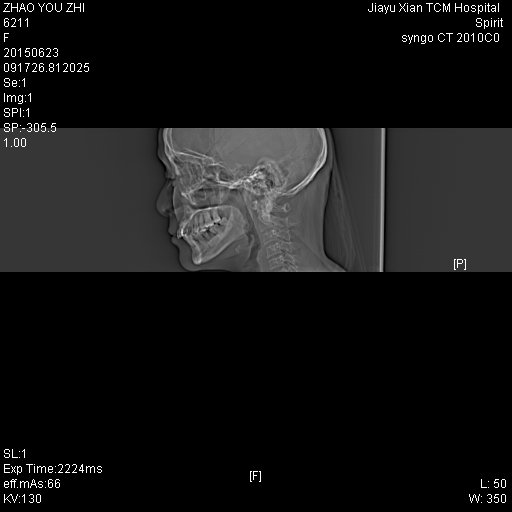

CT50731:女,40Y,乳突

左耳道长期流黄色液体,各位老师帮看下

左侧中耳乳突骨质密度增高,中耳鼓室、乳突气房可见弥漫性软组织密度影,上鼓室、乳突窦扩大,局部骨质破坏,内可见软组织影。印象:左侧慢性化脓性中耳乳突炎并胆脂瘤。

左侧慢性中耳乳突炎伴胆脂瘤形成。

左侧慢性中耳乳突炎(肉芽肿或胆脂瘤形成)。支持!

左侧慢性中耳乳突炎(肉芽肿或胆脂瘤形成)。

左侧慢性中耳乳突炎并胆脂瘤形成

左侧慢性中耳乳突炎并胆脂瘤.

左侧慢性化脓性中耳乳突炎并胆脂瘤